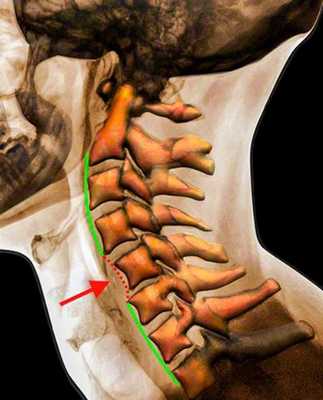

Рентгенограмма. Подвывих в шейном отделе позвоночника. Цветовая обработка изображения.

Рисунок 1 : Передний подвывих C4 по сравнению с C5 связан с увеличением зазора / дистракции фасеточного сустава. Вероятно, это связано с механизмом гиперфлексии.